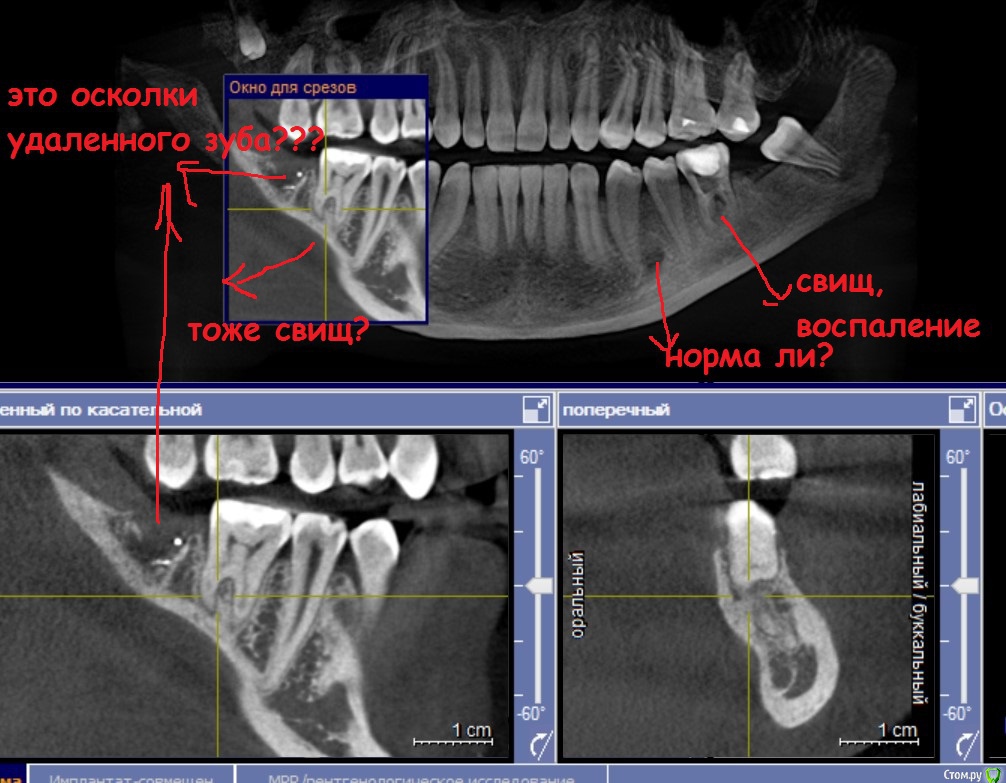

Milana34 Опубликовано 23 апреля, 2016 Поделиться Опубликовано 23 апреля, 2016 Добрый день, проконсультируйте, пожалуйста! Проблема - свищ, который сейчас лечу. Но его смотреть не нужно, шансы его спасти, как сказали несколько докторов ,есть, но малы. А вот симметрично ему (подписала стрелками) на зубе 6 с др. стороны - там тоже воспаление??? При пальпации как шишечка внутри… То ли лимфоузел, то ли слюнная железа… непонятно. И 7 удаленная - такое ощущение, что не до конца удалили… Переживаю... Ссылка на комментарий

Гарриевич Опубликовано 23 апреля, 2016 Поделиться Опубликовано 23 апреля, 2016 Норма ли? НормаВ остальном киньте ссылку на КТ, посмотрим Ссылка на комментарий

Doctor Vlad Опубликовано 24 апреля, 2016 Поделиться Опубликовано 24 апреля, 2016 скорее остатки пломб материала, ничего страшного Ссылка на комментарий

Doctor Vlad Опубликовано 24 апреля, 2016 Поделиться Опубликовано 24 апреля, 2016 слева где свищ))) деструкция костной ткани в фуркации 36 зуба- не норм Ссылка на комментарий